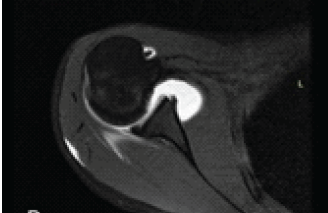

Rare Presentation of Chronic Anterior Instability with Concomitant Triad of Anterior Labral Periosteal Sleeve Avulsion, Hill–Sachs, and Humeral Avulsion of the Glenohumeral Ligament Lesions: A Case Report

Hady Ezzeddine , Rita Saad , Wendy Ghanem , Mohamad Badra , Ramzi Moucharafieh , Ziad Noun

………………………………p.133-139